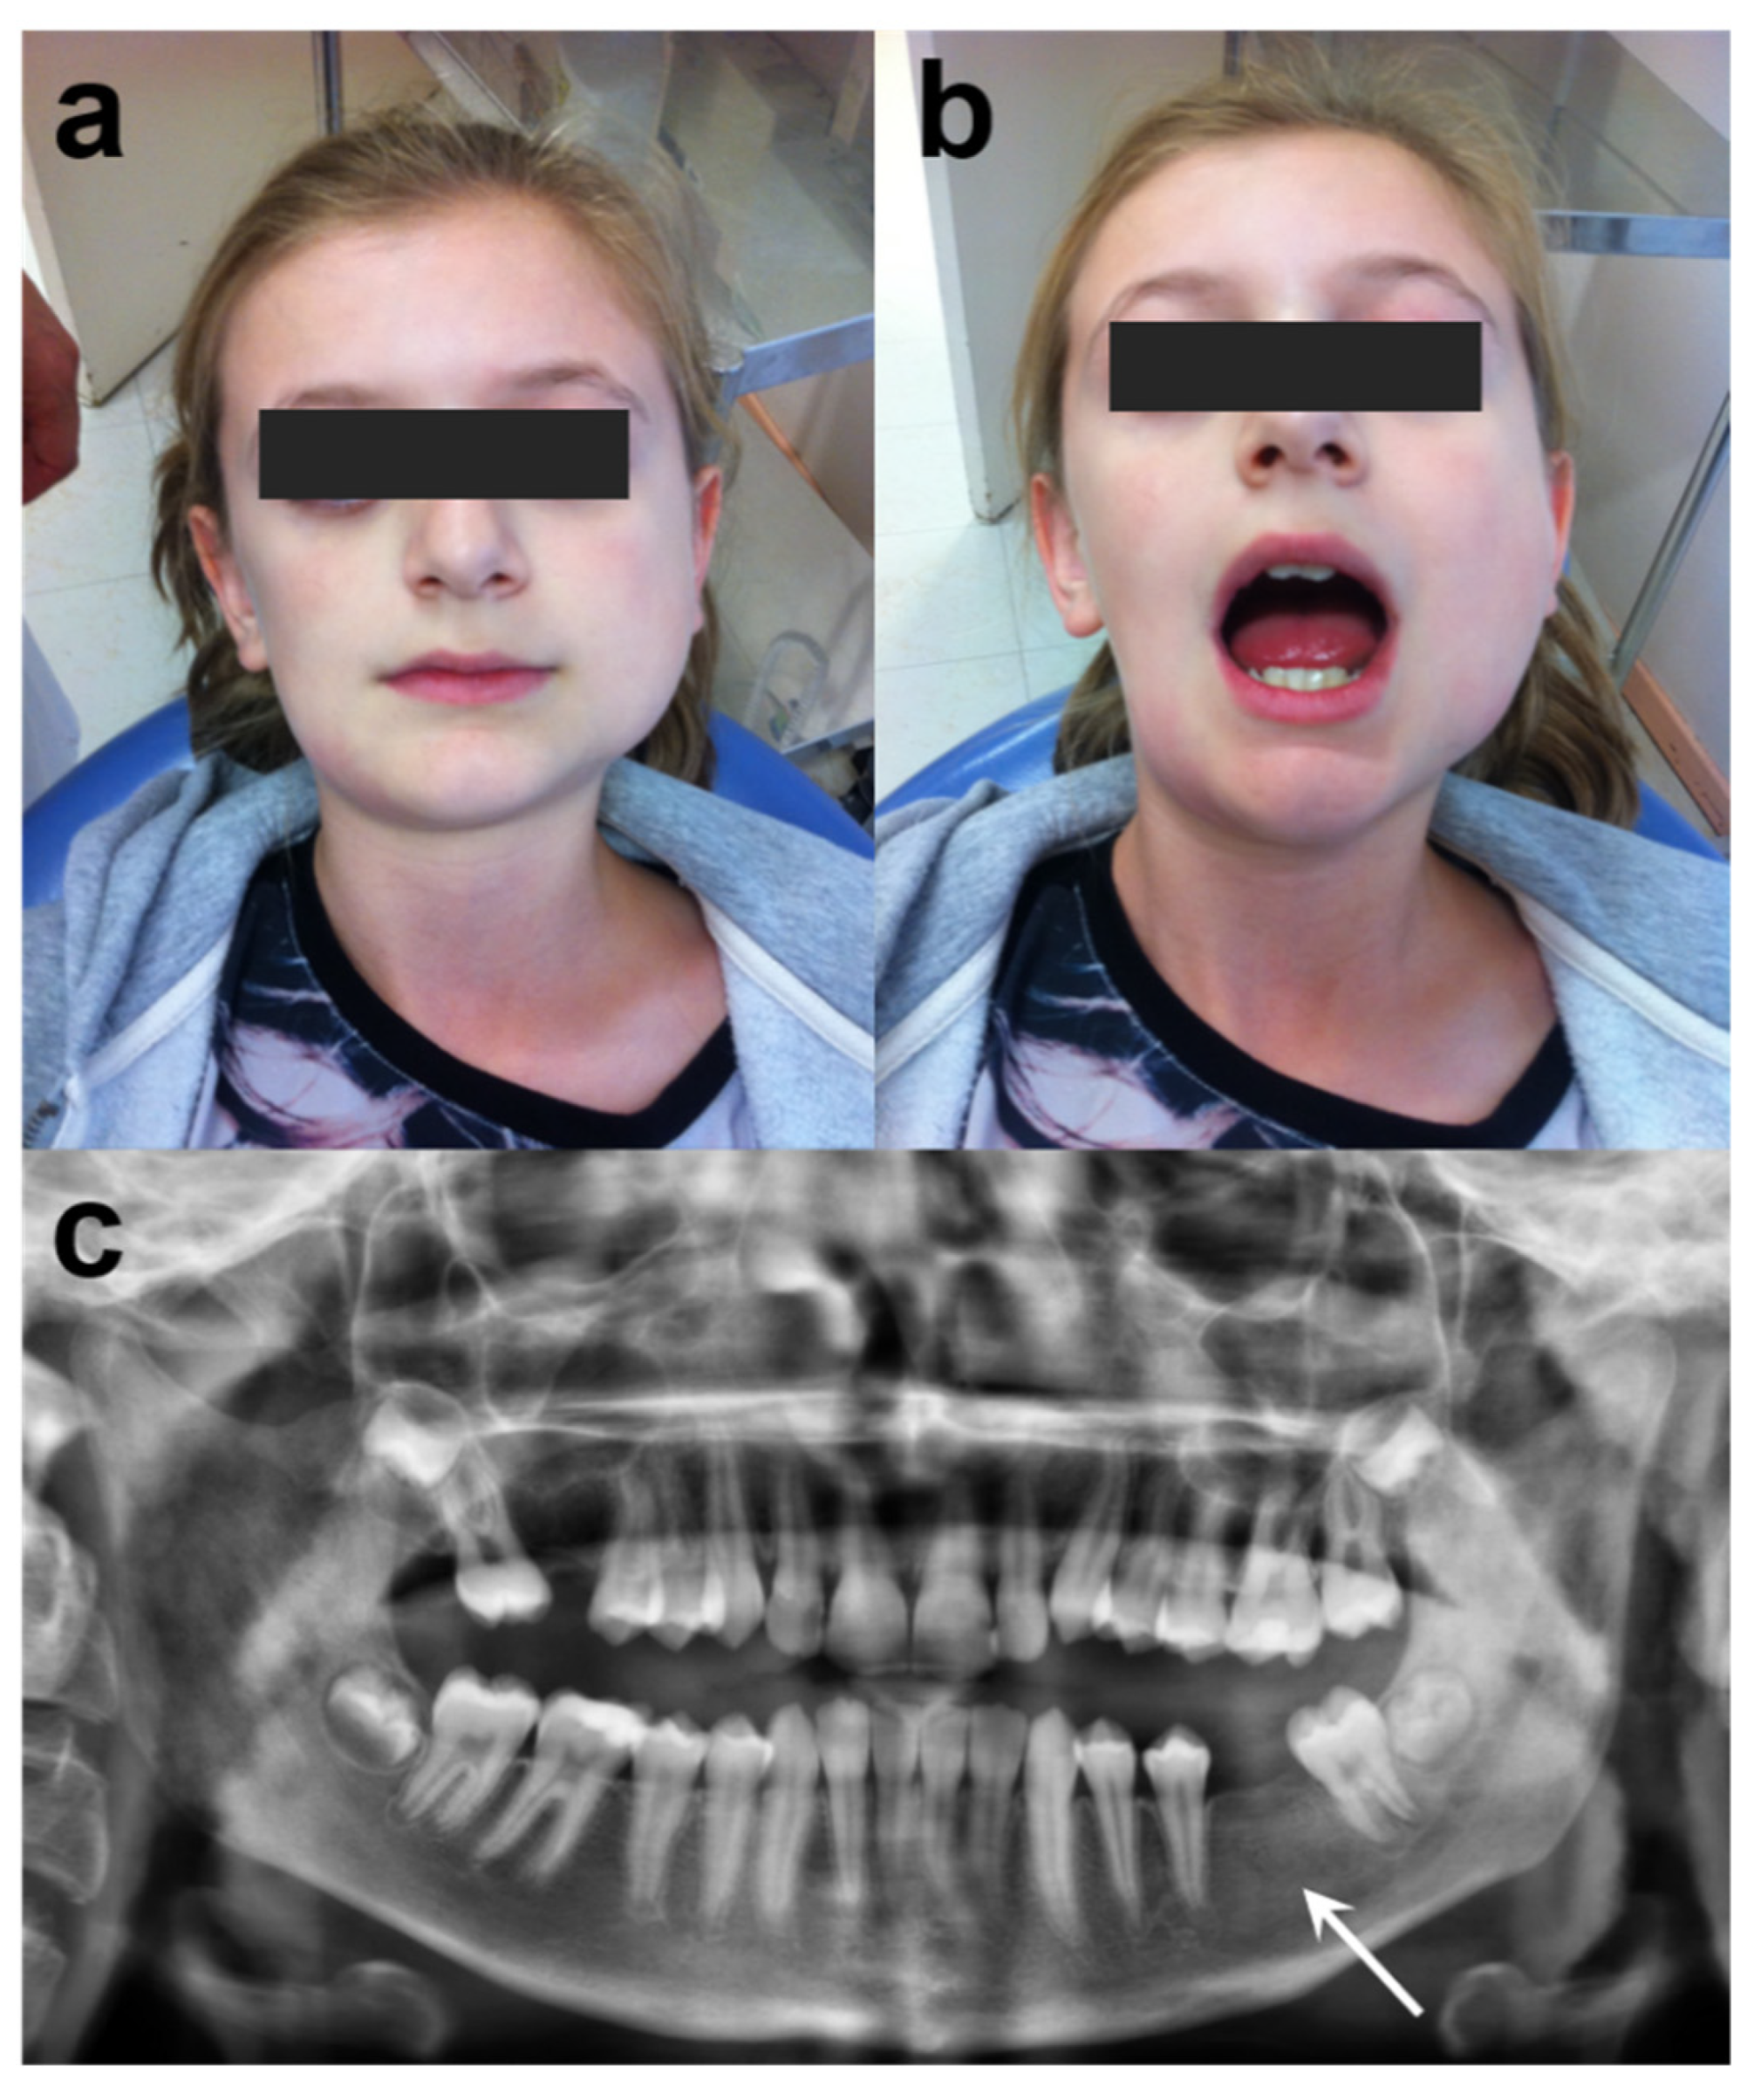

Based on these findings, a final diagnosis of chronic bacterial osteomyelitis was established. We initiated a 6-month course of oral antibiotic treatment with levofloxacin (500 mg, once a day) and cotrimoxazole (= trimethoprim/sulfamethoxazole, TMP/SMX) (400 mg/80 mg, two times a day). Periodic blood tests and renal function monitoring were performed with normal results. At 3 months, the patient was symptom-free. At 6 months, CBCT/CT scans showed a normal bone structure (Figure 4). At 2 years post-antibiotic treatment, no clinical or radiological relapse had been noted.

Figure 4. 3D computed tomography before and after antibiotic therapy: (ac) CBCT/CT scan before antibiotic therapy. (df) The corresponding CBCT/CT scan, 6 months after antibiotic therapy demonstrated complete bone healing. Bone sclerosis and osteolysis (mixt pattern) disappeared in mandible (d,e) and frontal bone (f). CBCT: Cone Beam Computed Tomography.